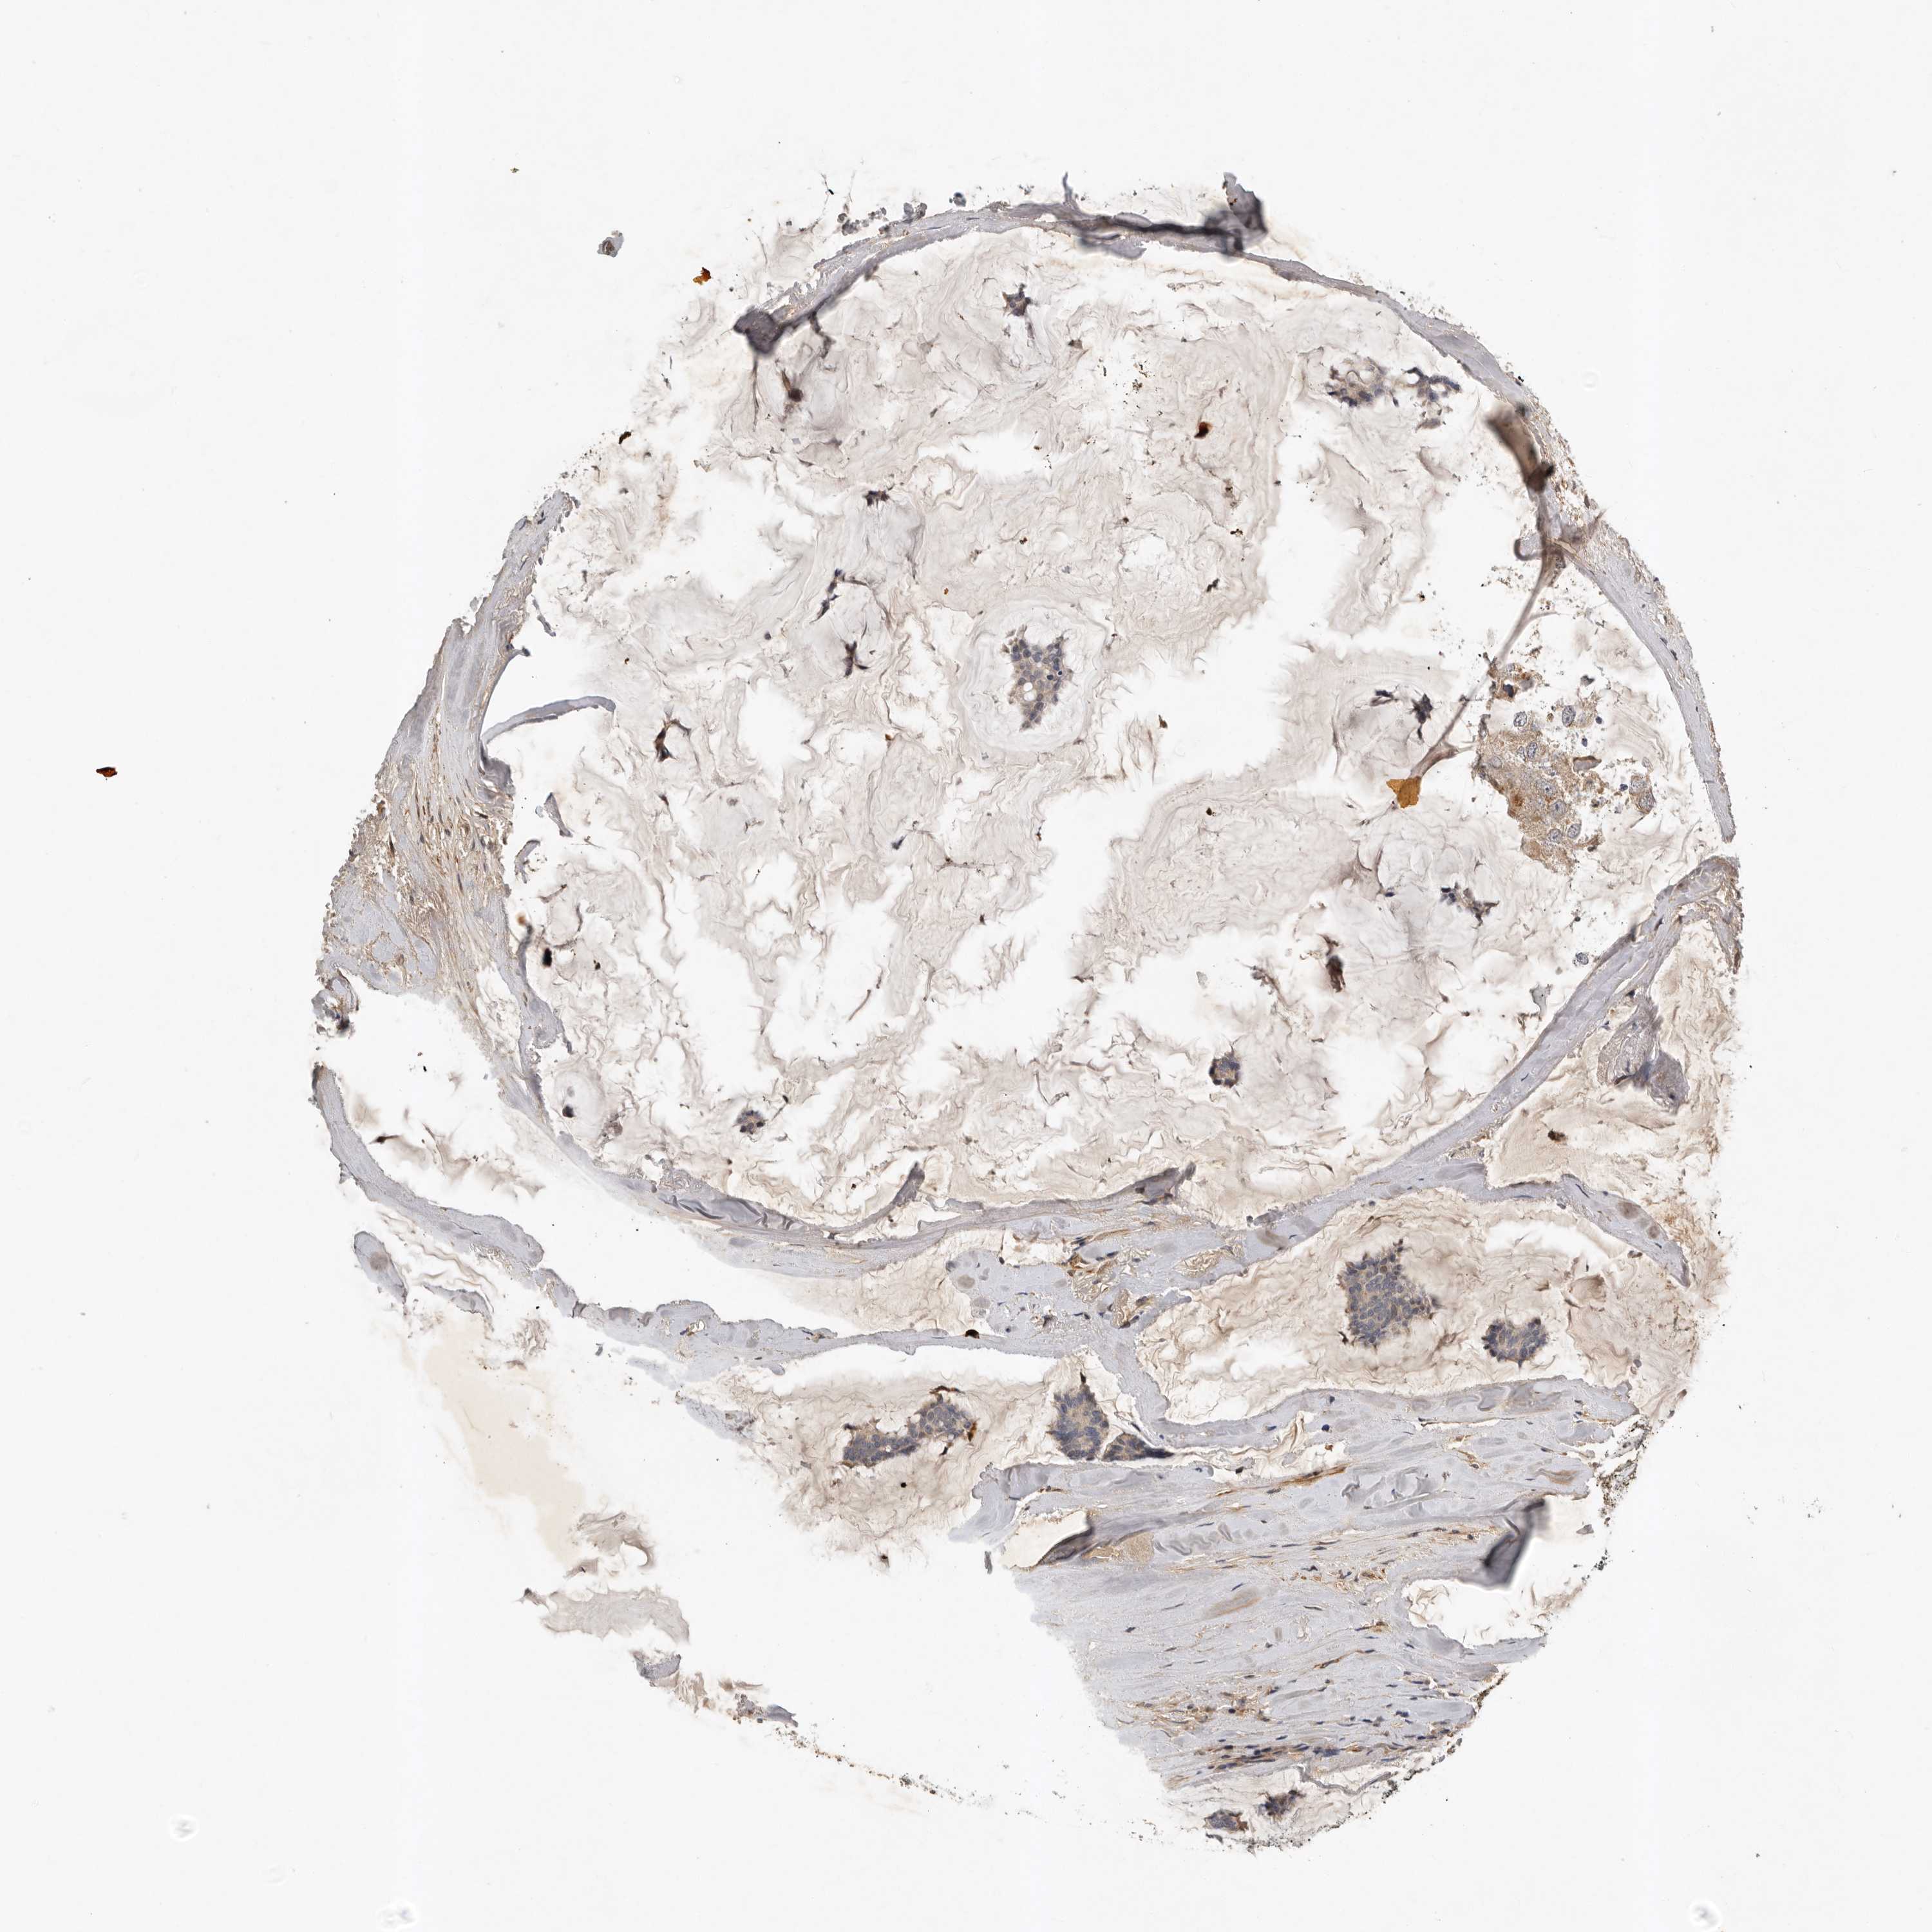

CANCER BREAST CANCER Show tissue menu

BRCA TCGA BRCA VALIDATION PROTEIN EXPRESSION